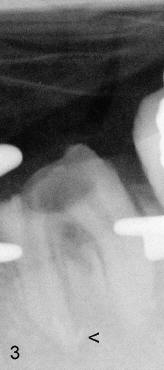

A 31-year-old otherwise healthy Chinese lady has had discomfort since RCT was done for the tooth #19 in home country ~2 years ago (Fig.1). Gutta percha (GP) appears to extrude both in mesial (<) and distal (<<) canals, surrounded by periapical radiolucency (PARL). Two carpules of 2% Lidocaine with 1:100,000 Epinephrine are used for RCT retreat. The patient does not experience any sharp pain during the first injection. Two rubber dams are used due to the short clinical crown of #19 (Fig.2,3). Fig.2 shows master cones (30/.06 M, 40/.06 D) after removal of existing gutta percha using Chloroform. It appears that extruded mesial GP remains outside the apex (< in Fig.2). It is confirmed after removing master cones (< in Fig.3). Working length is controlled by Apex locator during canal re-shaping using GT rotary files. In attempt to remove apparent GP in mesial canal(s) and extruded one outside the apex, #15 hand file is reused at WL+1mm with Chloroform for one or twice for each canal. After adjusting distal GP length, cold lateral condensation is finished with AH26 plus paste and pre-existing PFM crown is recemented (Fig.4). It is apparent that the previously extruded GP is not removed (< in Fig.4).